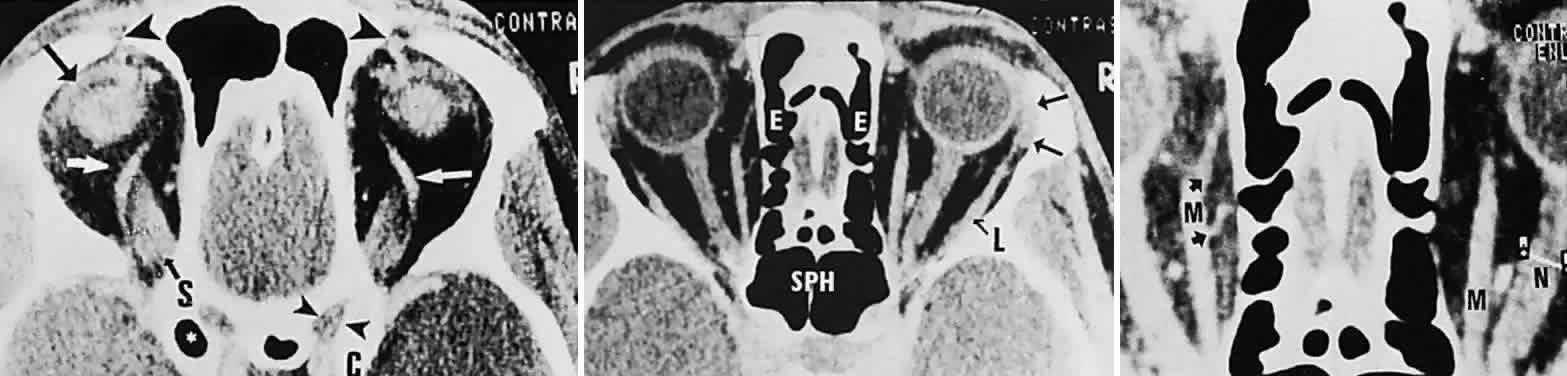

Computed tomography (CT) is presently the single most productive modality for analyzing orbital bones, with which the following structures may be visualized: the bony confines of the orbit and surrounding sinus structures; the lacrimal bony canal; the globe and lens; the intraorbital portions of the optic nerve; and the extraocular muscles, especially the horizontal and superior recti (Fig. 16). Moreover, CT with contrast enhancement discloses the full configuration and location of masses with respect to other orbital structures, principally the relationships to muscle cone, optic nerve, and lacrimal gland. In several particular instances, the location, configuration, and degree of contrast enhancement of lesions may strongly suggest a distinctive tumor type (Fig. 17) or inflammation (e.g., cavernous hemangioma, optic glioma, lacrimal gland tumor, dermoid cyst, mucocele, perioptic meningioma, single or multiple muscle thickening),65–67 but no firm histopathologic diagnosis may be inferred by CT characteristics alone.

Fig. 16. Contrast-enhanced CT scan of normal orbits. Top. Superior orbit section shows superior ophthalmic veins (white arrows), superior rectus origin (S), left levator muscle complex (black arrow), position of trochlea and tendon of superior oblique muscles (large arrowheads), right optic canal (small arrowheads), and anterior clinoid (C). (*, pneumatized left anterior clinoid.) Middle. Midorbital section shows ethmoidal sinus complex (E), sphenoidal sinus (SPH), lacrimal gland (arrows), and lateral rectus (L). Bottom. Enlargement shows left medial rectus (M), with anterior (top arrow) and posterior (bottom arrow) ethmoidal arteries; note cursor across optic nerve on right (N).

Graves' disease is the overwhelming single most common cause of single or multiple extraocular muscle thickening (Fig. 18; see also Volume 2, Chapter 12, Figs. 28 and 30); inflammatory myositis is considerably less frequent, and muscle metastases are quite rare. Passive congestive myopathy also accompanies arteriovenous shunts and lesions of the superior orbital fissure and cavernous sinus, where orbital venous return is obstructed. The capacity of CT to detect minor to moderate changes in muscle diameter is perhaps limited,70 and standardized A-scan ultrasonography seems more sensitive and practical.71

Fig. 18. CT scan in Graves' disease. Top. Axial section shows massively enlarged horizontal recti (M, medial) with packed apex. Bottom. Coronal section demonstrates enlarged medial (M), superior (S), and inferior (I) recti.